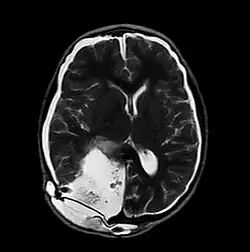

| MRI of Pseudomeningocele in 8 years old male patient | |

A pseudomeningocele is an abnormal collection of cerebrospinal fluid (CSF) that communicates with the CSF space around the brain or spinal cord. In contrast to a meningocele, in which the fluid is surrounded and confined by dura mater, in a pseudomeningocele, the fluid has no surrounding membrane, but is contained in a cavity within the soft tissues.